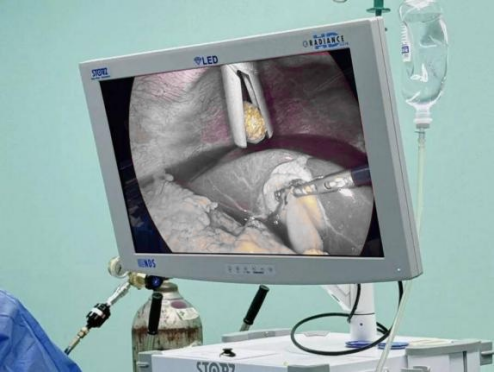

双镜联合

微创保胆取结石

一位胆囊结石患者来院就医,希望在取出结石的同时保留胆囊生理功能,检查显示其胆囊功能正常、胆总管通畅,符合保胆指征。普外科王兆太主任团队为其制定“腹腔镜+胆道镜双镜联合”方案,通过双镜协同操作,清晰探查胆囊内部情况,精准取净结石,完整保留胆囊的储存、浓缩胆汁功能。术后患者疼痛症状彻底消失,避免了盲目切胆可能引发的消化功能紊乱,收获患者高度认可。